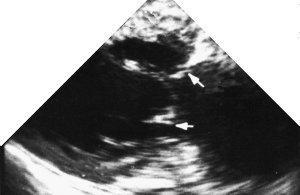

What papillary muscle is seen here?

Posteromedial Papillary Muscle